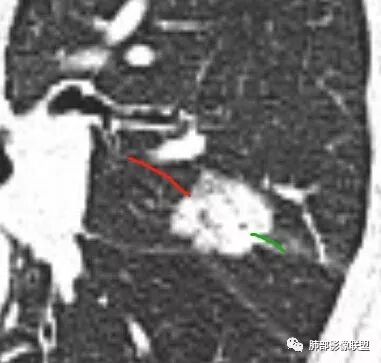

马宁强:考虑肉芽肿性病变,隐球菌可能彭君:左肺上叶舌段混合毛玻璃密度结节 边缘清 有分叶毛刺 斜裂胸膜凹陷征 考虑腺癌可能王秀仙:左肺上叶结节,部分边缘磨玻璃清晰,有分叶毛刺,支气管通过并扩张,其外侧小叶间隔不规则增厚,胸膜牵拉,考虑腺癌。鉴别慢性炎症。田园晚风:左肺上叶多个小结节融合呈分叶状,可见叶间裂牵拉,考虑腺癌张帅:左肺上叶后段结节,内可见支气管穿过,病灶周围有少许毛刺,病灶边缘有浅分叶,对叶间胸膜有牵拉,部分位置呈对叶间胸膜推移。考虑为恶性病变,腺癌?。杨泽锋:混合型磨玻璃结节,边缘有膨隆、有凹陷,明显的胸膜牵拉,考虑腺癌可能大;内部支气管通畅、似乎有鬼脸征,所以鉴别隐球菌Lotus:病灶内部有结节感,这个大小似乎是次级肺小叶的大小,考虑炎性,有冠位最好了。但是胸膜牵拉有些恶性提示心包右侧软组织密度影考虑心包隐窝Yiren Sishui(厶水伊人):叶间裂有膨隆有凹陷,考虑恶性,腺癌可能

徐婕:同意恶性腺癌可能岁月:女,56;空泡,分叶毛刺,牵拉线,胸膜凹陷征,有强化,浸润性腺癌。THINKER:左舌见结节,膨胀为主,部分收缩,分叶丶短丶硬毛刺,牵拉斜裂,有小空泡,支气管穿行,有强化,常规腺癌丽:左肺上叶近胸膜下结节,胸膜牵拉,边缘膨隆,并可见深分叶及毛刺,内有空泡,增强后可见强化,倾向腺癌淘时光:混合磨玻璃结节,实性部分较多,内见支气管穿行,腺癌首先考虑了…☀:左肺上叶结节影,实性,边缘分叶征,其内可见空泡,部分膨胀生长,局部叶间裂牵拉上移,叶间裂光滑增厚,首先考虑肿瘤黄棘:左肺上叶结节,边缘彭隆, 周围磨玻璃影边界清,内部可见扩张支气管,叶间胸膜牵拉,考虑腺癌心灵鸡汤:左肺上叶舌段近斜裂处混合性结节,以实性成分为主,有分叶、毛刺,牵拉邻近叶间、脏层胸膜,增强有强化,影像学上看偏恶性,分类LU-RADS 4C类,MIA浸润性腺癌可能,鉴别肉芽肿性病变、隐球菌,请老师指点!THINKER:这个如果是腺癌,应该是IAC了,过MIA了,个人看法,罗老师一切∮随缘:左肺叶裂胸膜下结节,边缘收缩弱,周围有GGO,边界清楚,形态欠规则,其内似有支气管穿行,增强扫描轻度均匀强化,考虑1肉芽肿性病变(隐球,炎性假瘤)2:浸润性腺癌Clover:考虑腺癌,实性为主混合有少许边界清晰ggo,边缘膨隆,其内支气管气象不规则,有收缩力。Coke with ice:还有一个疑问请教一下:这个是混合磨玻璃结节还是实性结节?个人倾向于后者。心灵鸡汤:有部分磨玻璃Coke with ice:实性结节周围GGO初学者:实性,周围有毛玻璃晨:有浅分叶,有毛刺,有叶间裂牵拉,内有囊泡,考虑腺癌。初学者:稍等,我等会开电脑看,但是感觉和你们一样,感觉是一个典型病例来着Coke with ice:这个人我也倾向于腺癌。但是诊断腺癌还有一个比较疑惑的地方,肺窗病变密度显示比较实,但是纵隔窗病灶范围明显比肺窗小,腺癌可以解释的通吗?张小兵:混合磨玻璃结节,内见支气管穿行,分叶,胸膜牵拉从凹陷处进入,腺癌首先考虑小微:

Coke with ice:这里是不是脐凹征呢?对诊断方向很重要。待老师们指点。

脐凹、分叶

Coke with ice:@南边 老师这里是不是脐凹征这个好像和胸膜相连,不是标准的脐凹征南边:定义上是指血管、支气管从凹陷处进入远端是出去进入、出去是两个概念

近肺门侧是进入,意味着血管支气管顶住,导致局部的肿瘤生长受限;出去是指血管穿过肿瘤从远端延伸出去所以我认为有价值,但不是脐凹征。